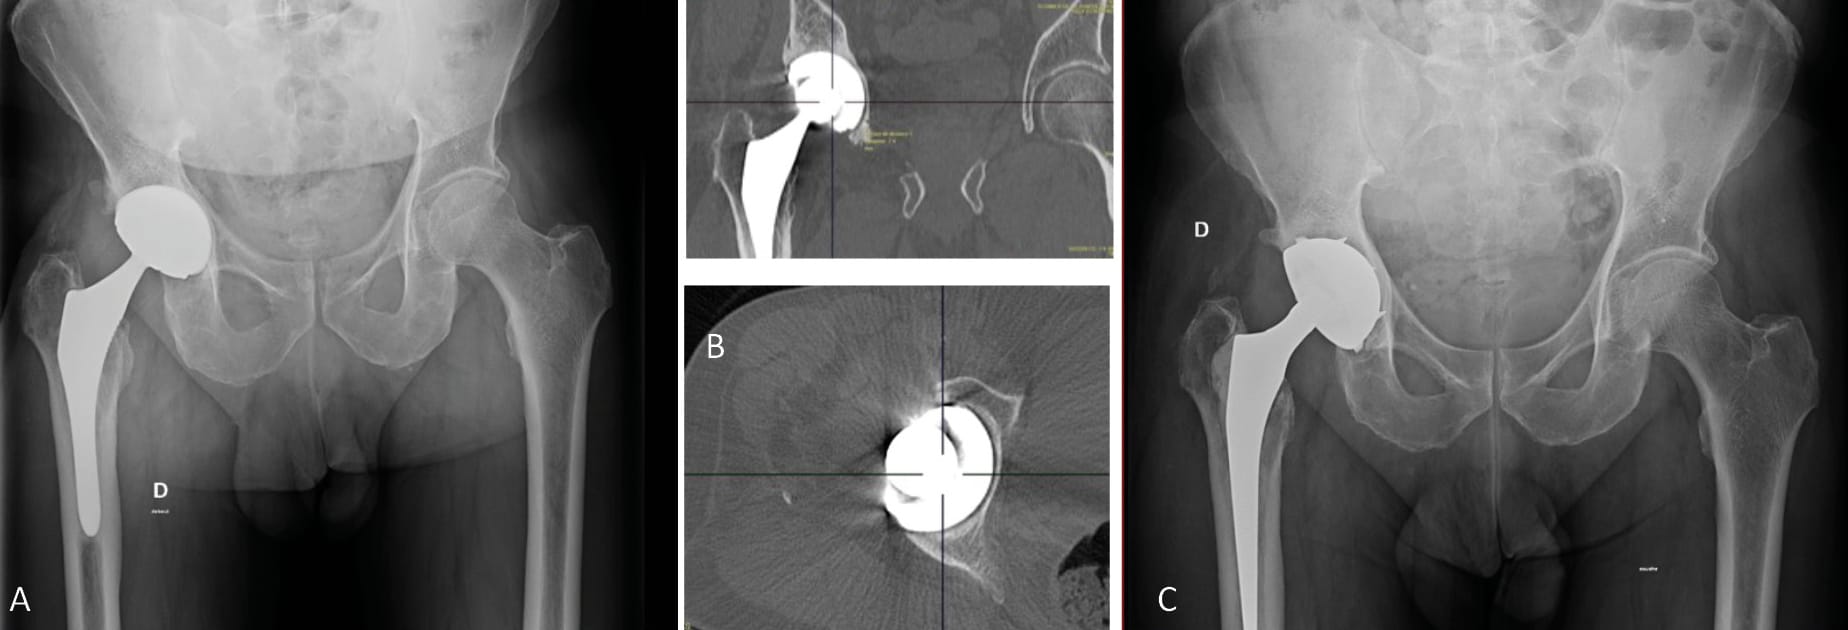

The first option is to use a cementless DM cup either with (Figure 2) or without spikes (Figures 3 and 4) or a peg with a minimum implant size of 40, depending on the manufacturer, and a technically demanding fitting process, resulting in good cup stability for patients with bone defects or poor bone quality, which can, in some cases, leave fewer options. This implant is a first line option indicated particularly in patients with implant instability and moderate bone loss. (Figures 2, 3, 4)

Another option is the modular dual mobility cup. This type of implant remains useful in cases of moderate bone loss and allows the surgeon to optimise the primary fixations (screws) while still taking advantage of the DM concept. The advantages as well as the potential complications specific to this device have been outlined previously [23] Epinette J-A, Coulomb R, Pradel S, Kouyoumdjian P. Do Modular Dual Mobility Cups Offer a Reliable Benefit? Minimum 5-Year Follow-Up of 102 Cups. J Arthroplasty 2022;37:910–6. https://doi.org/10.1016/j.arth.2022.01.025.. We should also point out the risk of liner malseating, although this does not appear to have an impact on the medium term survival curve [50], Bengoa F, Howard LC, Neufeld ME, Garbuz DonaldS. Malseating of Modular Dual Mobility Liners: High Prevalence in Revision Total Hip Arthroplasty. J Arthroplasty 2023:S0883540323003443. https://doi.org/10.1016/j.arth.2023.03.094.[51], Guntin J, Plummer D, Della Valle C, DeBenedetti A, Nam D. Malseating of modular dual mobility liners. Bone Jt Open 2021;2:858–64. https://doi.org/10.1302/2633-1462.210. BJO-2021-0124.R1.[52] Siljander MP, Gausden EB, Wooster BM, Karczewski D, Sierra RJ, Trousdale RT, et al. Liner malseating is rare with two modular dual-mobility designs. Bone Jt J 2022;104-B:598–603. https://doi.org/10.1302/0301-620X.104B5. BJJ-2021-1734.R1. (Figure 6).